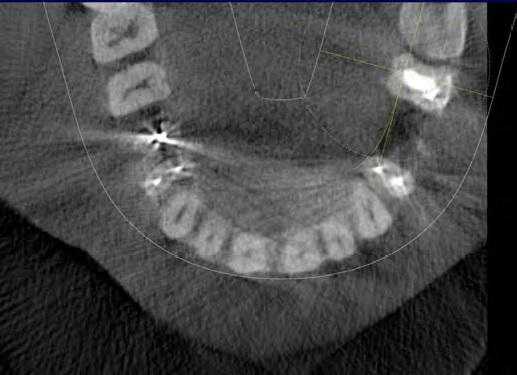

4. Резорбция корня

Резорбция корня это утрата твердых тканей зуба в результате активности остеокластов. Это может происходить в рамках физиологического или патологического процесса. Корневая резорбция может быть классифицирована на внешнюю и внутреннюю, в зависимости от локализации процесса относительно поверхности корня. Первые данные о внутренней резорбции получены в 1830. В сравнении с внешней резорбцией внутренняя является весьма редким процессом, этиология которого до конца не изучена. Точность КЛКТ при определении дефектов поверхности хоть и является более высокой по сравнению со стандартной техникой, но, все же, не идеальна и повышается при повышении разрешения вокселей снимка. КЛКТ также показала свою состоятельность при оценке постортодонтической апикальной резорбции, в частности корней латеральных резцов верхней челюсти при импактных клыках.

На КЛКТ внешняя резорбция проявляется как неравномерная рентгенопрозрачность и интактный канал зуба, внутренняя же резорбция выглядит как четкий очаг без прослеживания корневого канала.

КЛКТ с успехом применяется для определения внутренней резорбции и дифференциации ее от внешней. Обычная рентгенография часто не может выявить верный объем распространения, локализации и источник резорбтивного процесса. КЛКТ помогает в определении с тактикой лечения, а также предлагает составить верный прогноз на основе активности и распространенности поражения. И лечение, и результат лечения таким образом становятся более предсказуемыми.